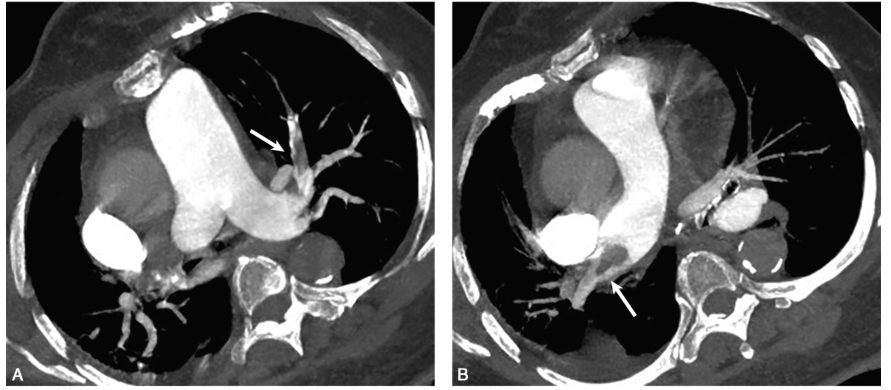

胸部CTA:双侧肺动脉及其分支多发充盈缺损(图1)。

图1肺动脉CTA:左肺上叶肺动脉充盈缺损(A);右肺动脉主干及右肺中间干动脉充盈缺损(B)(白箭),胸主动脉蛋壳样钙化